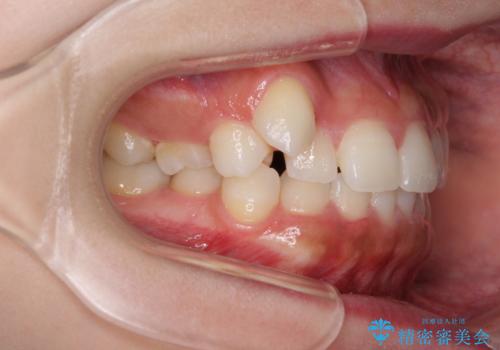

- 八重歯を気にして来院された患者様です。

本来であれば八重歯の隣後方の歯を抜歯するのですが、その後ろの歯が乳歯であり後続永久歯もなかったため、乳歯を抜去することとしました。

前から5番目の乳歯は、後続永久歯である小臼歯と比べて幅径が大きいため、移動に時間がかかりましたが、きれいに仕上げることができました。